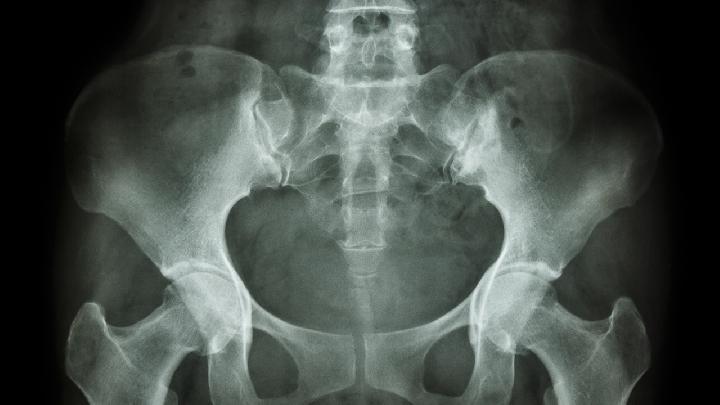

股骨粗隆间骨折患者多为老年人。首先要注意全身情况,防止骨折后卧床不起等各种危及生命的并发症,如肺炎、褥疮、泌尿系感染。骨折治疗的目的是防止髋内翻畸形。具体治疗方法应根据骨折类型、移位、患者年龄和全身情况采用不同的方法。以下是中医治疗股骨粗隆间骨折的方法。

先以2%普鲁卡因15~20ml血肿内麻醉,助手固定骨盆,手术人员握住患肢,沿纵轴方向拉伸,骨折有向下摩擦,重叠移位矫正,然后根据骨折类型,患肢放置在适当位置,外翻骨折,内翻骨折将骨折远端向内推,内翻骨折保持中立位置。X线位满意后,将患肢放在牵引架上,行骨或皮肤牵引。牵引重量一般为4~5kg,要防止远端向上移位。5~6周后,在外展夹板保护下,离体持双拐不负重步行,7~8周可根据骨折愈合情况,改为单拐负重行走。